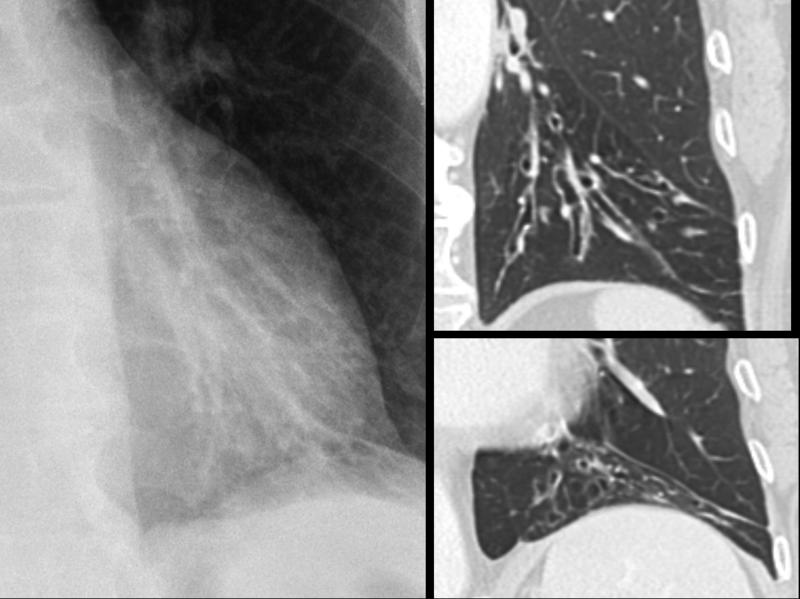

Gallery Bronchiectasis Chronic airway disease

Chronic airway disease